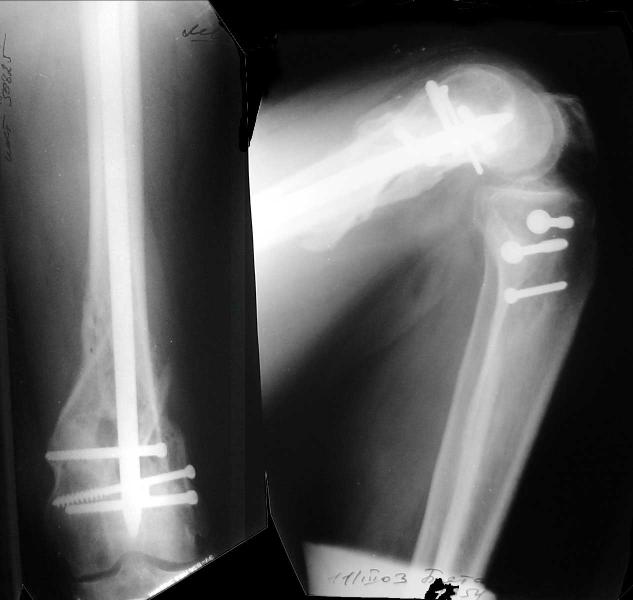

This is what we have done... As generally true for LISS look at the bone not the hardware.

There are two more srews above. The one not completely in got damaged head.

Look what we would have done.